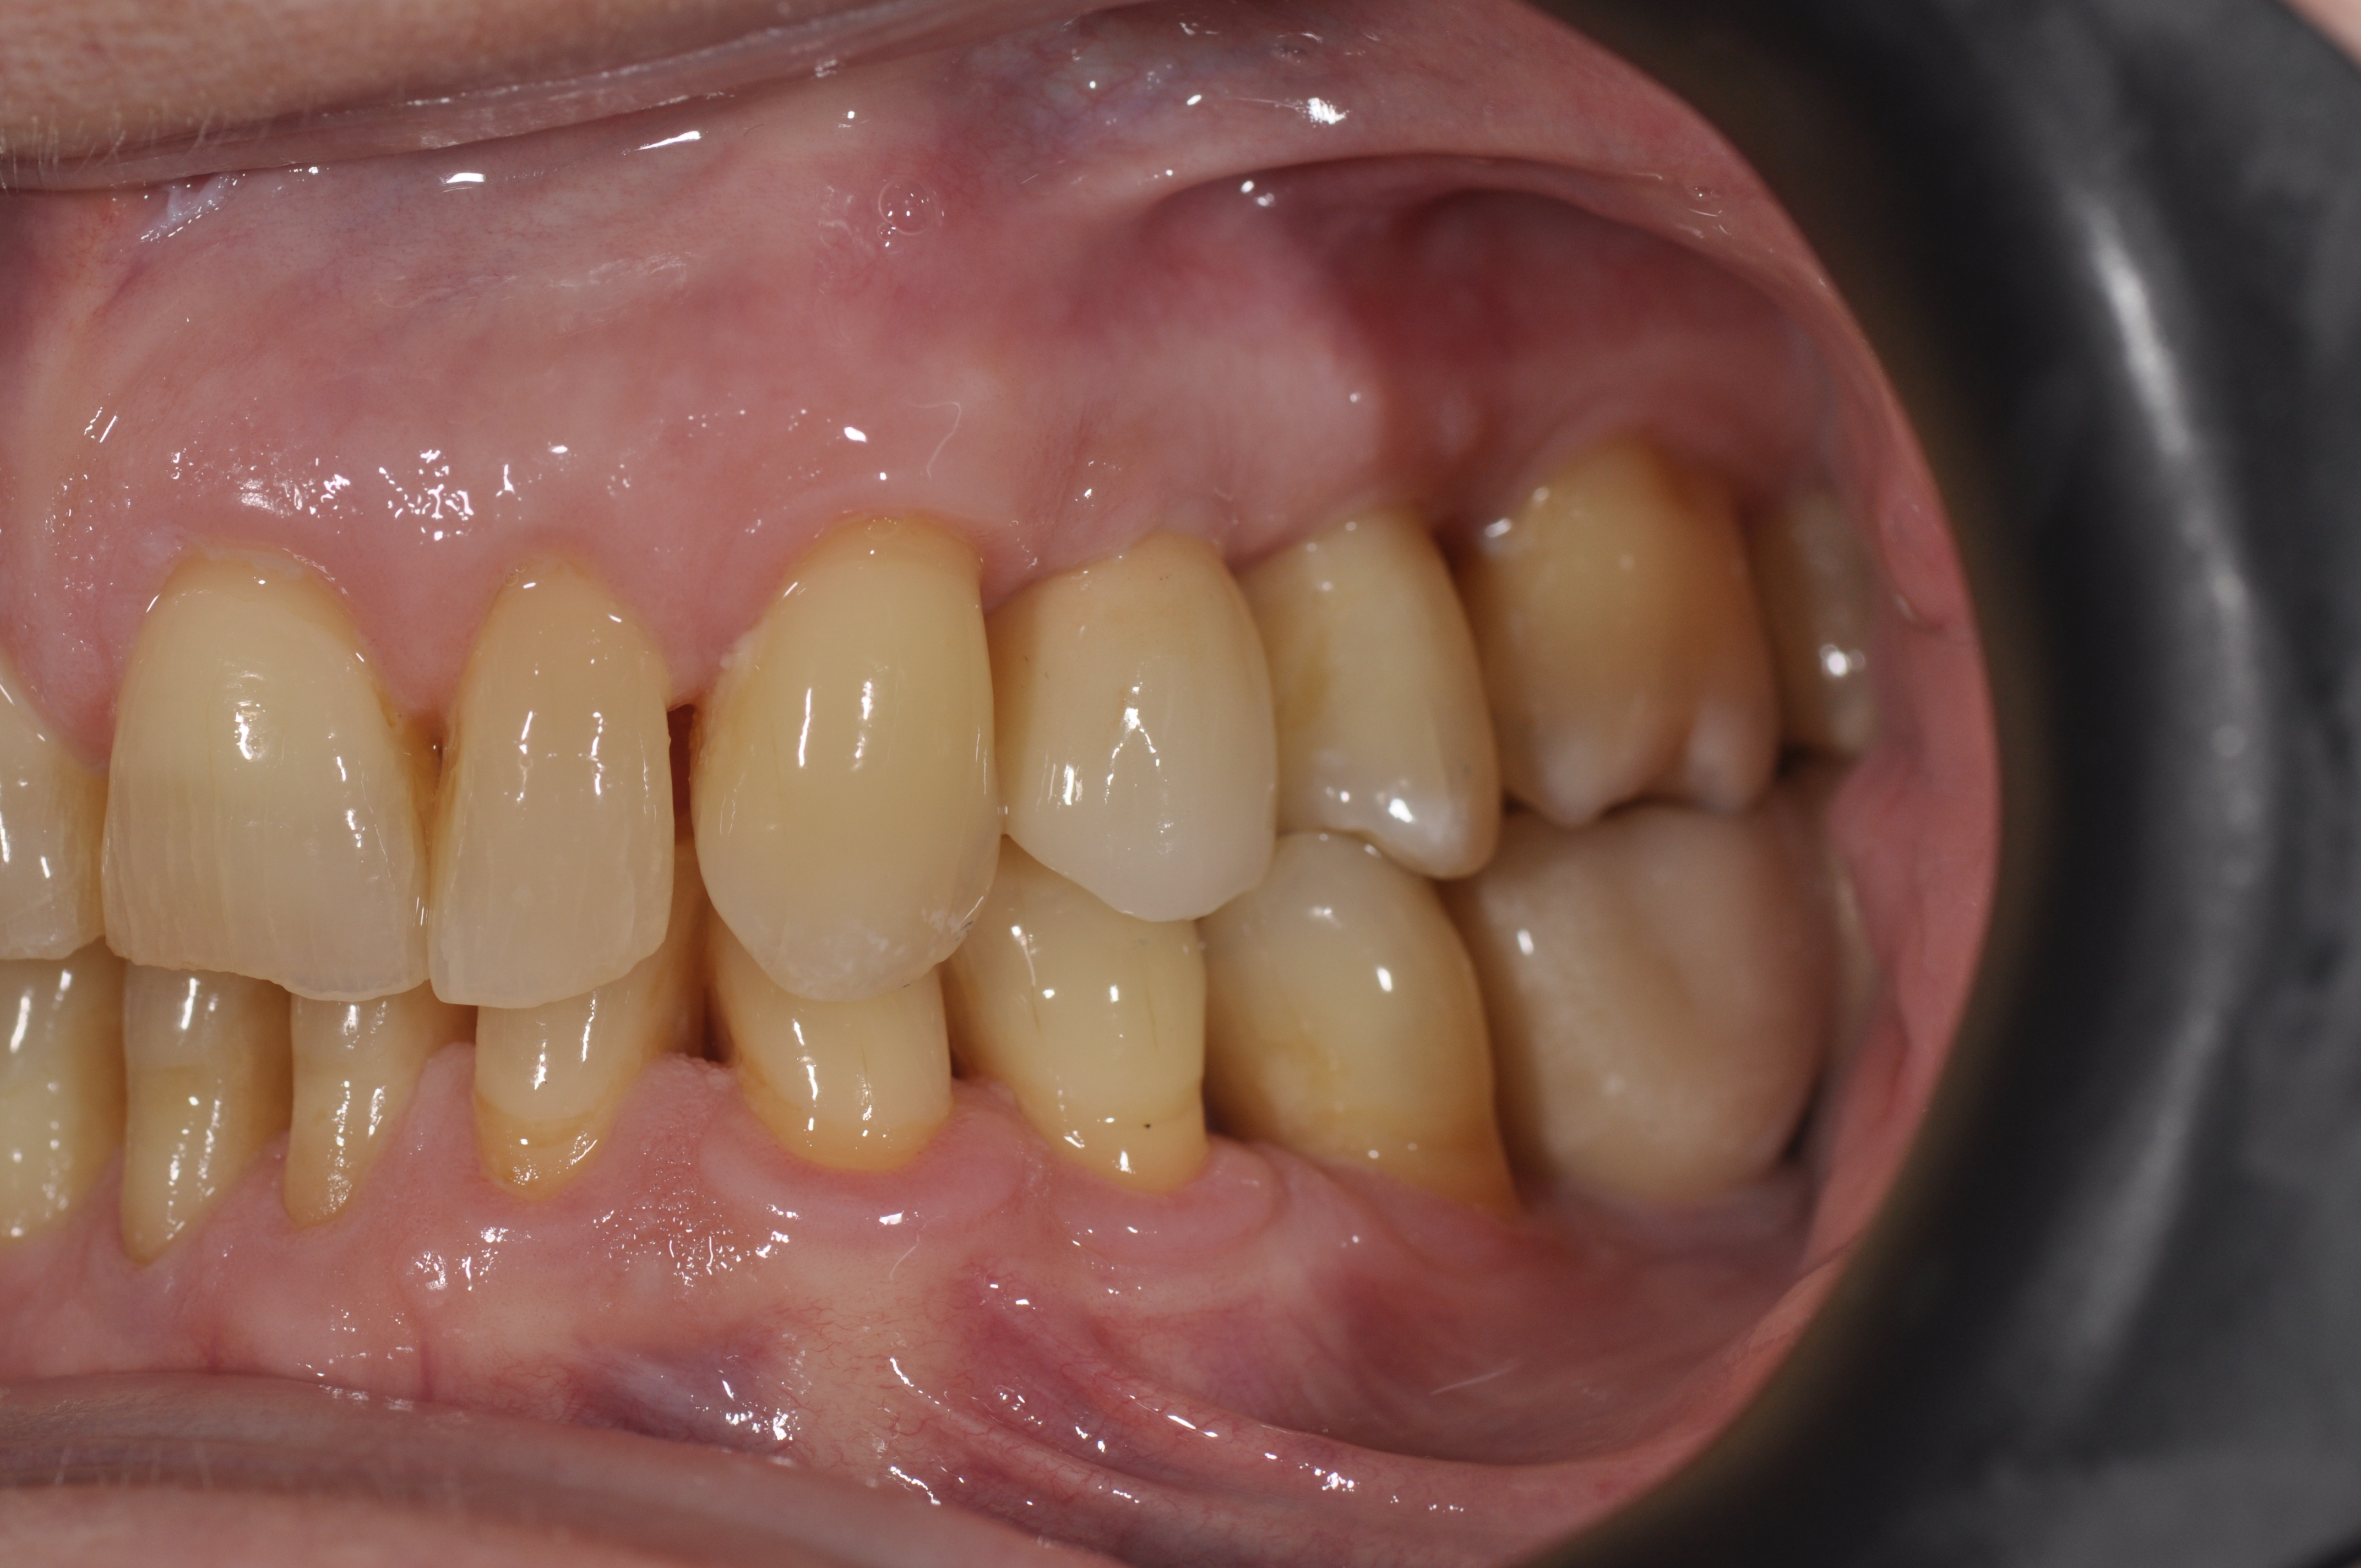

Prótesis Dental en Segovia

En Clidentse, el Dr. César Segovia Miguel es quien se encarga de la especialidad de prótesis Fija o Removible, tanto sobre diente, como prótesis sobre Implantes. Porque tu salud bucodental es nuestra prioridad, queremos hacer de tu tratamiento una experiencia positiva.